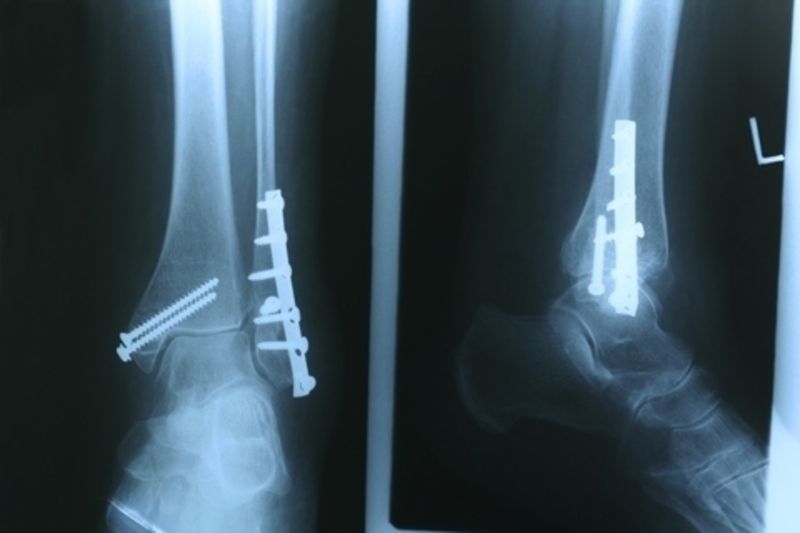

Forradalmasíthatja a sebészetet egy új eljárás, amelyben száz százalékos selyemből készült csavarokat használtak törések rögzítéséhez - ismertette a BBC News.